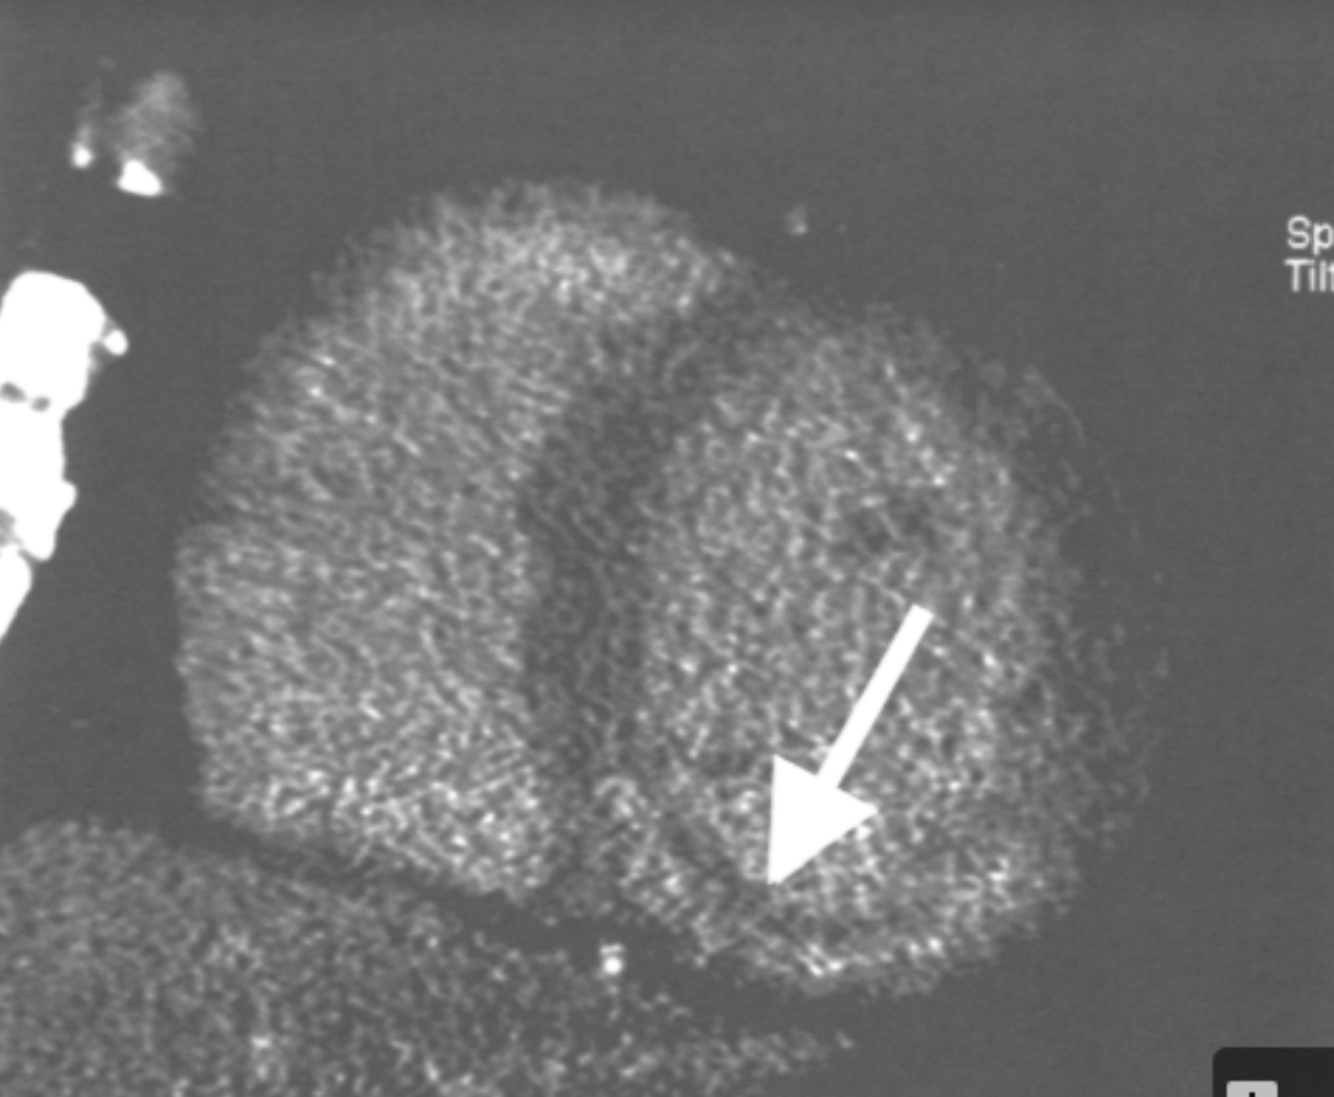

Describe the finding:

Microvascular obstruction